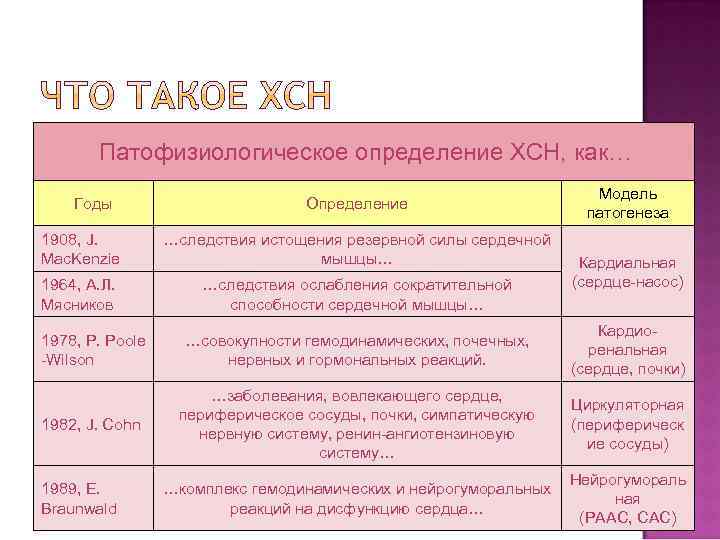

Патофизиологическое определение ХСН, как… Годы Определение 1908, J. Mac. Kenzie …следствия истощения резервной силы сердечной мышцы… 1964, А. Л. Мясников …следствия ослабления сократительной способности сердечной мышцы… Модель патогенеза Кардиальная (сердце-насос) 1978, P. Poole -Wilson …совокупности гемодинамических, почечных, нервных и гормональных реакций. Кардиоренальная (сердце, почки) 1982, J. Cohn …заболевания, вовлекающего сердце, периферическое сосуды, почки, симпатическую нервную систему, ренин-ангиотензиновую систему… Циркуляторная (периферическ ие сосуды) …комплекс гемодинамических и нейрогуморальных реакций на дисфункцию сердца… Нейрогумораль ная (РААС, САС) 1989, E. Braunwald

Патофизиологическое определение ХСН, как… Годы Определение 1908, J. Mac. Kenzie …следствия истощения резервной силы сердечной мышцы… 1964, А. Л. Мясников …следствия ослабления сократительной способности сердечной мышцы… Модель патогенеза Кардиальная (сердце-насос) 1978, P. Poole -Wilson …совокупности гемодинамических, почечных, нервных и гормональных реакций. Кардиоренальная (сердце, почки) 1982, J. Cohn …заболевания, вовлекающего сердце, периферическое сосуды, почки, симпатическую нервную систему, ренин-ангиотензиновую систему… Циркуляторная (периферическ ие сосуды) …комплекс гемодинамических и нейрогуморальных реакций на дисфункцию сердца… Нейрогумораль ная (РААС, САС) 1989, E. Braunwald